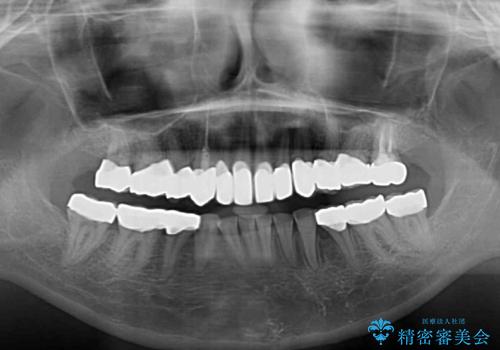

- 一時期の拒食症に伴い歯が酸で溶けてボロボロになってしまったとのことで来院された患者様です。

酸によりエナメル質の大半が溶けており、下顎前歯以外は酷いむし歯のような状態でした。

当初はほとんどの歯をむし歯治療のようにオールセラミッククラウンにて補綴治療を行う予定でしたが、仮歯に置き換えた時点で、口元の突出感や下顎前歯の叢生が気になるとのことで、上下左右の第一小臼歯4本を抜歯したワイヤー装置での抜歯矯正を行うこととしました。

矯正治療終了後に、残った歯をオールセラミッククラウンにて補綴治療を行うこととしました。